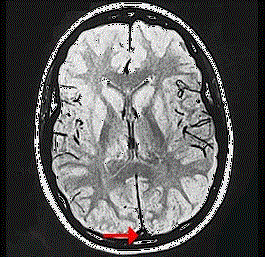

如图箭头所示为大脑哪个部位 ( ) A、窦汇B、横窦C、下失状窦D、直窦E、上矢状窦

问题 如图箭头所示为大脑哪个部位 ( )

选项 A、窦汇 B、横窦 C、下失状窦 D、直窦 E、上矢状窦

答案 E